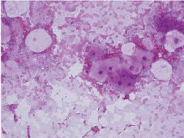

Figure 10. Keratocyst- parakeratotic cells-aspiration cytology.